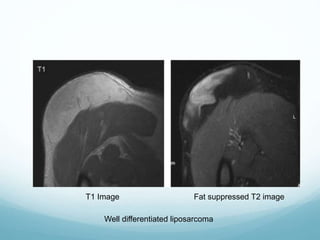

Well differentiated liposarcoma

T1 Image Fat suppressed T2 image

 Well differentiated to moderately differentiated

liposarcomas have areas of signal consistency with

normal fat but admixed with non-fatty signal